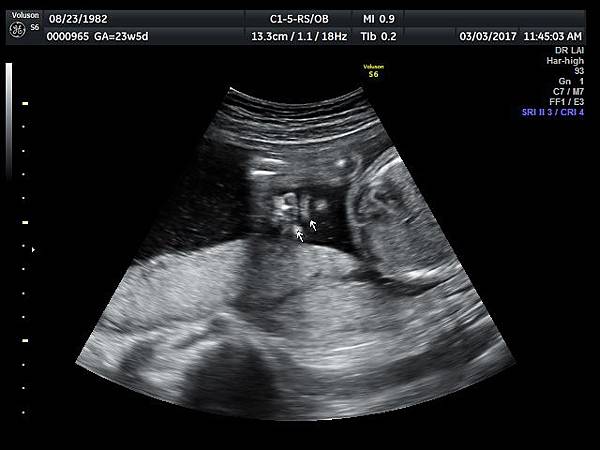

孕兒診所備忘錄 221 fetal bilateral cleft lip and palate

fetal bilateral cleft lip and palate